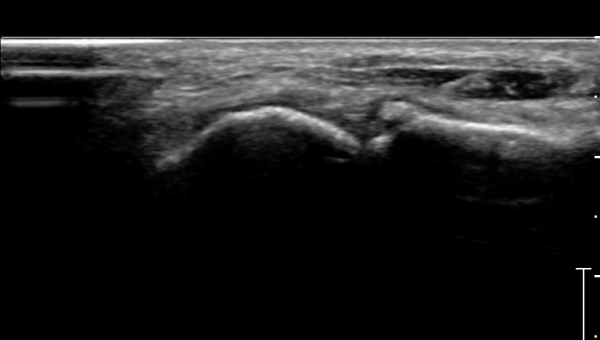

Á¾°ñÀÔ¹æ°ñ°üÀý Á¾´Ü¸é°Ë»ç»ó Á¾°ñ Àü¹æµ¹±â °ß¿­°ñÀý°ú Á¦4ÁßÁ·°ñ °ß¿­°ñÀýÀÌ °üÂûµÈ´Ù(»çÁø 2).